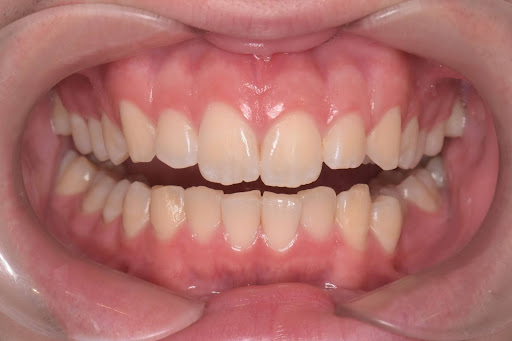

こちらは術後の写真となります。

綺麗な歯並びになっております。